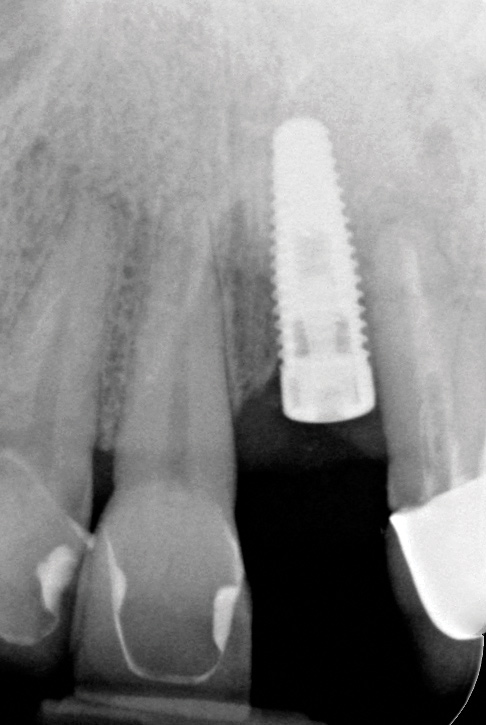

The following case report provides an example of this case scenario: A 55-year-old Caucasian female presented with a chief complaint of tenderness of 1-week duration around a single implant-supported crown in tooth No. 19 position; the implant and restoration had been placed approximately 2 years prior.

Clinical examination showed 2 mm of buccal recession with a shallow vestibule and absence of keratinized attached gingiva against the crown with 8 mm of circumferential pocketing accompanied by bleeding upon probing (Figure 15 and Figure 16). A periapical radiograph showed a symmetrical vertical osseous defect causing the loss of 50% of the bone around the implant (Figure 17). Because the patient had made a significant investment of time and finances to replace her lost tooth with the implant, she desired that the implant and restoration be retained, if feasible.

Fig 17. Radiograph showed symmetrical infrabony defect affecting 50% of the implant surface.

Figure 17